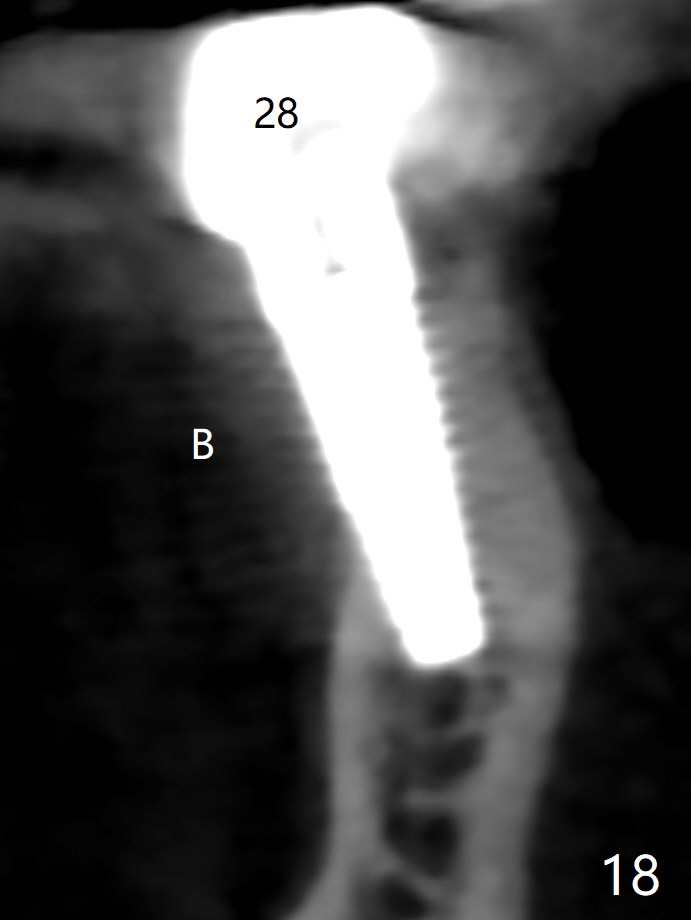

The edentulous ridge at #30 is narrow (Fig.1). After ridge reduction, osteotomy is initiated with 1.2 mm drill for 10 mm; the mesial osteotomy is to be changed (Fig.2 red line). Using a 1.2 mm drill placed in the distal osteotomy (Fig.3 D), the mesial osteotomy changes in trajectory with subsequent placement of a 2.5x10(4) mm 1-piece implant. Since the mesial implant is high in occlusion, the cuff of the distal implant is changed to be 2 mm (Fig.4 (shorter black line)). Panoramic X-ray is taken to show no violation of the Inferior Alveolar Canal (Fig.5 red dashed line). These two 1-piece implants are slightly lingually placed (Fig.6). The crestal bone around the implants resorbs without thread exposure 5 months postop (Fig.7). Impression is taken for a splinted crown (Fig.8-12). There is no metal show around the 2.5 mm 1-piece implants 6 months postop (advantage) vs. that at #28 and 29 (Fig.13). Bitewing is taken post cementation to determine whether residual cement is present (Fig.14). There is periodic swelling and pain in the lower right quadrant 2 years post cementation (Fig.15). In fact periimplantitis appears to have developed at #28 (Fig.16) with loss of the buccal bone (Fig.17,18). The buccal bone loss is less at #29 (Fig.19) and #20 (Fig.23) and no at #30 mesial and distal implants (Fig.20,21). A much smaller implant will be placed lingually at #28 immediate (Fig.24,25).